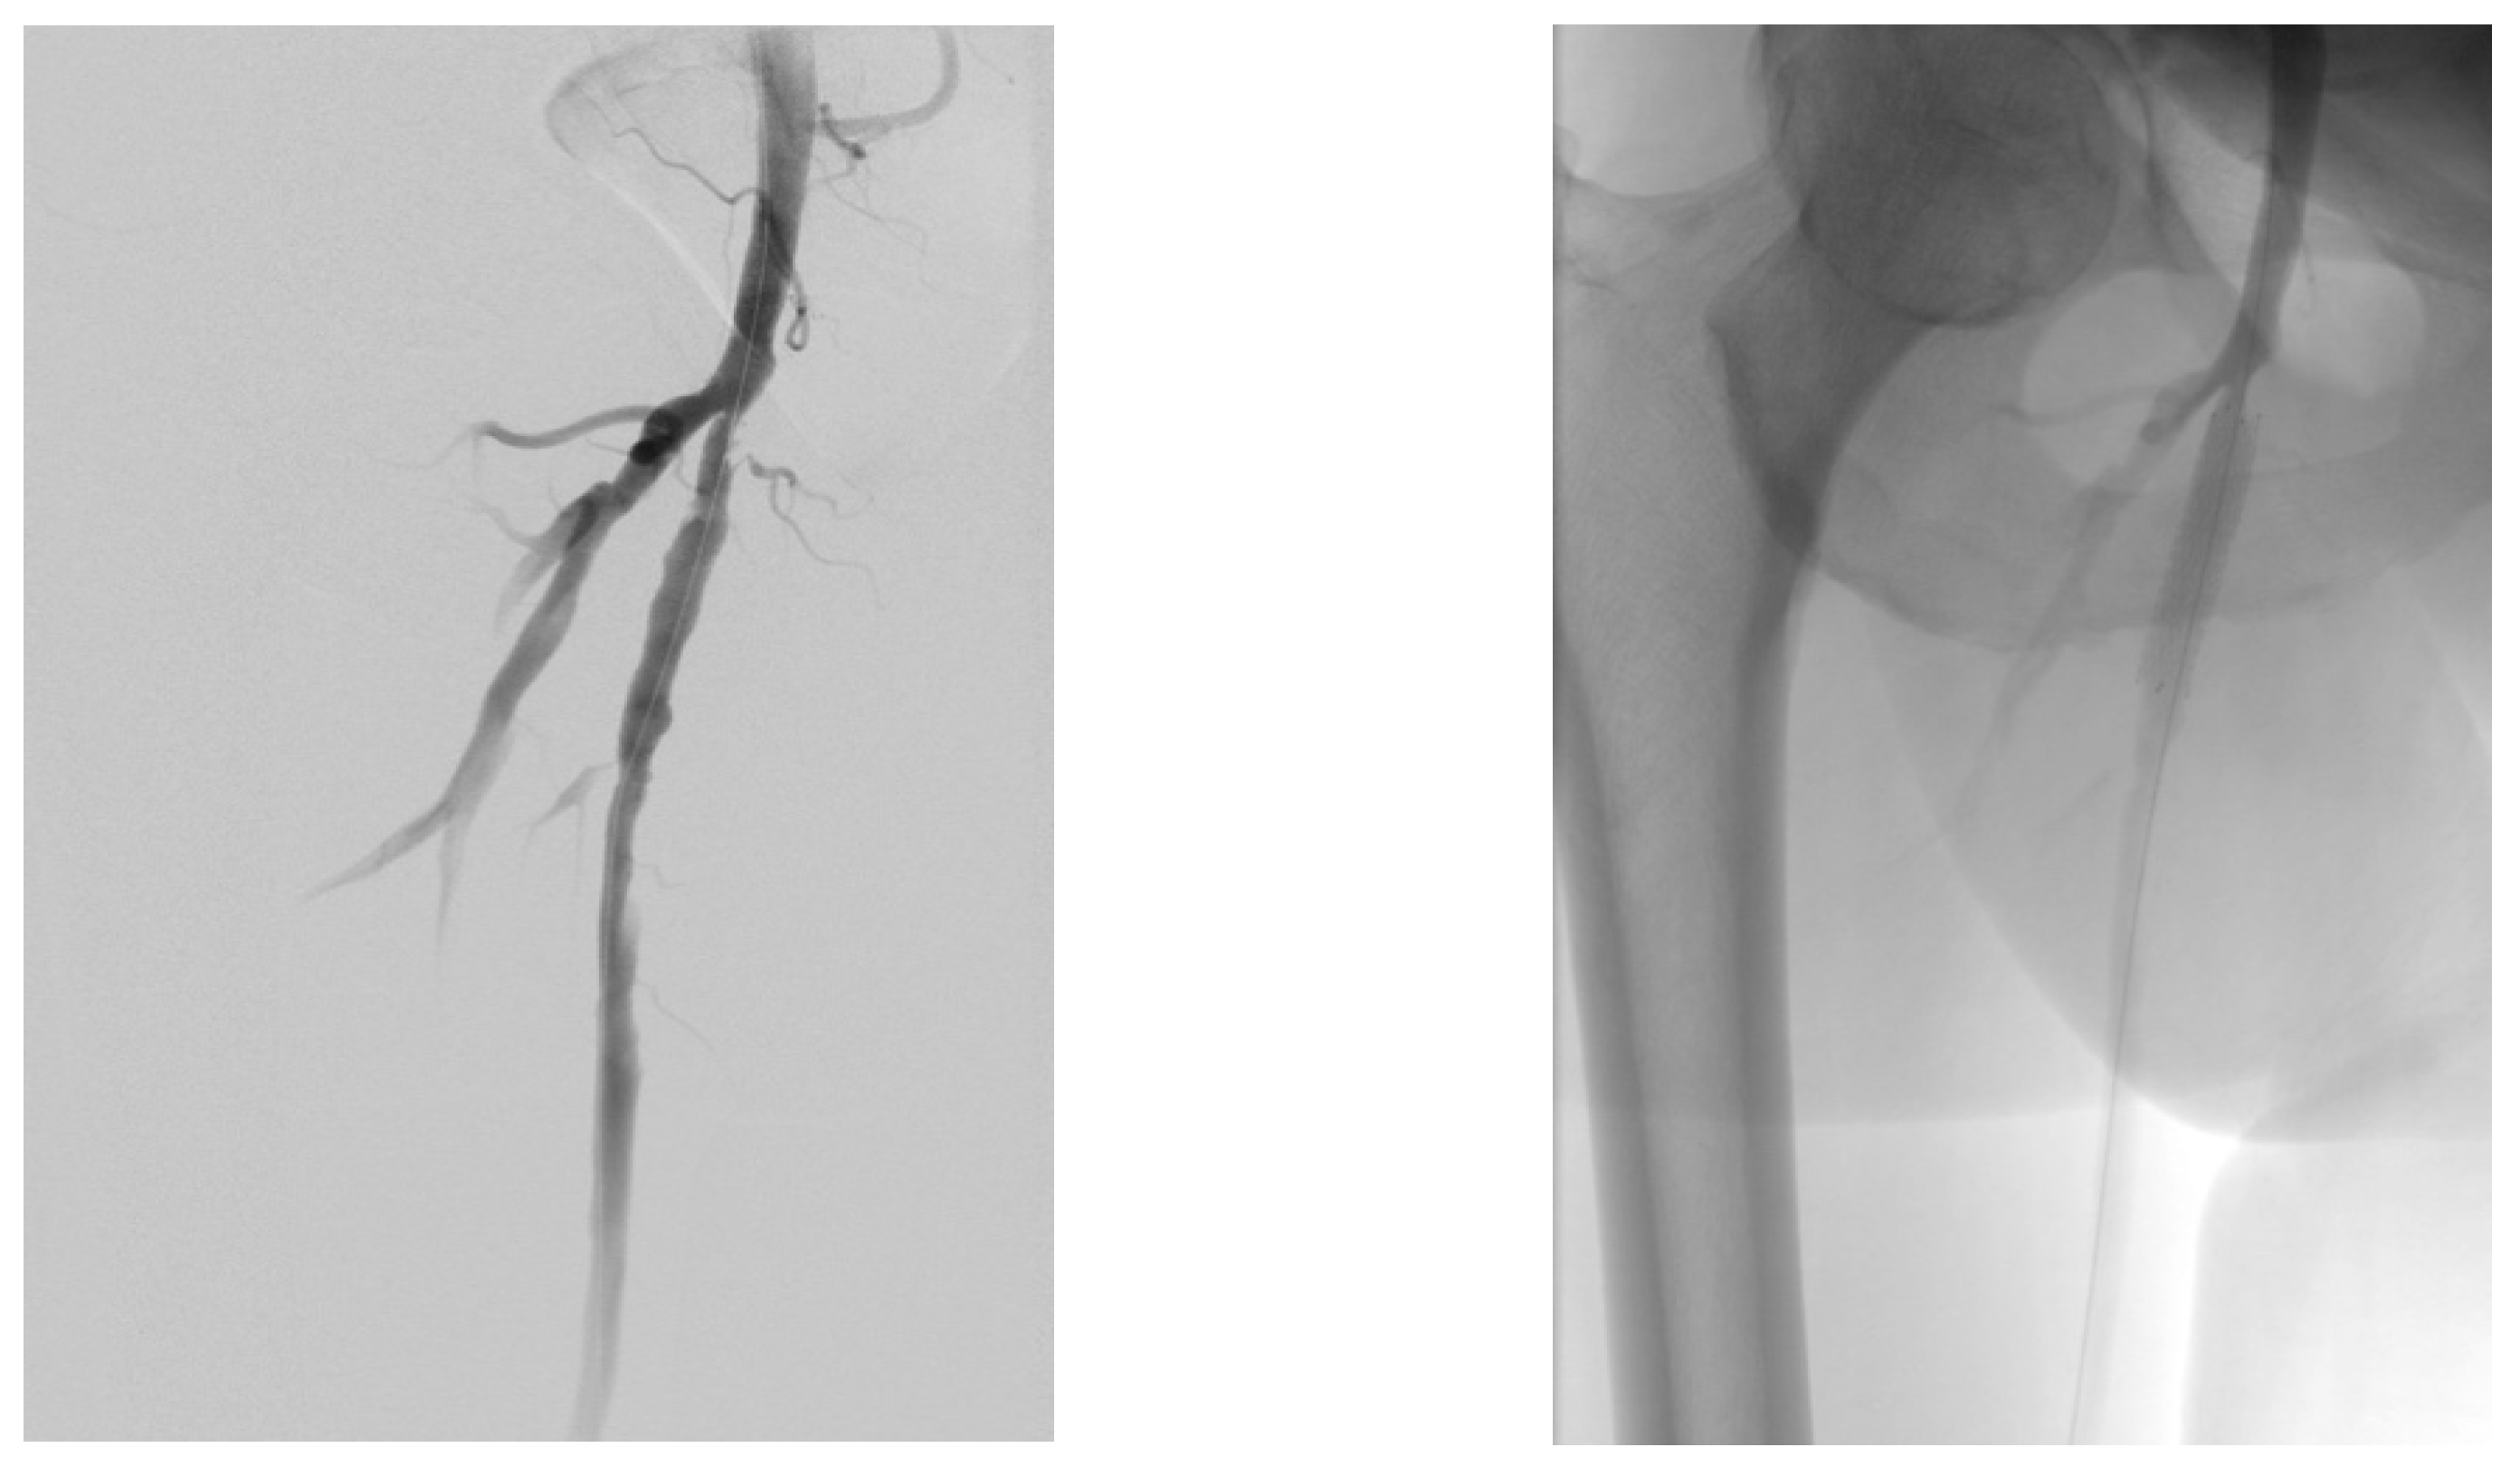

4.1. Case 1—Direct Revascularization-Minor Amputation

4.2. Case 2—Indirect Revascularization-Major Amputation